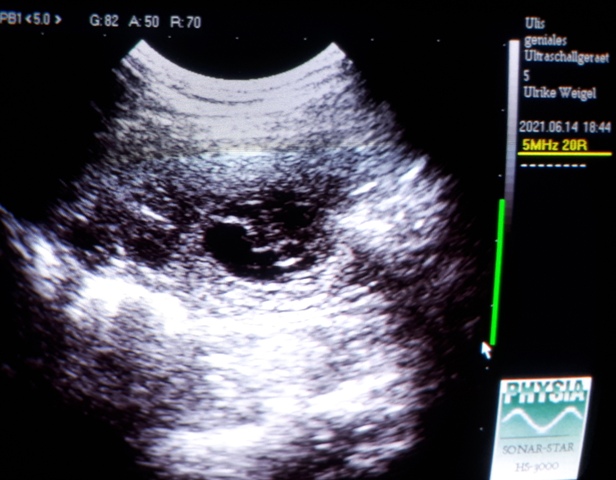

14.06.2021 - 26. Tag der Trächtigkeit

Heute geht es Phoebe viel besser!

Wir haben nochmal nachgeschaut :)

Unsere Lillis entwickeln sich prächtig und sind ganz schön gewachsen:

Wie ihr vielleicht erkennen könnt, gehen direkt neben der kleinen Furchthülle, beim

weiterführen des Schallkopfs, die nächsten Fruchthüllen auf (..links..)

Man kann ein Teil der Nabelschnur und im Hintergrund den Welpen erkennen.

Hier sieht man einen anderen Zwerg etwas besser :)

Bis morgen :)